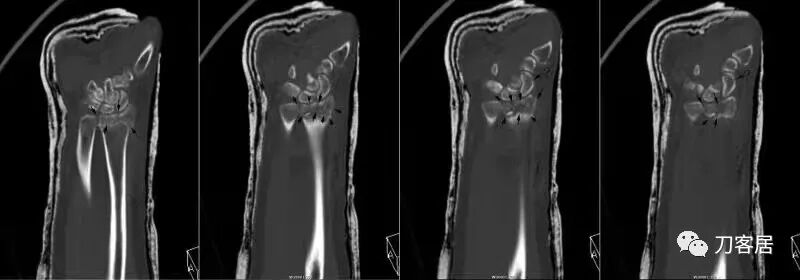

2021年7月22日晚,上海美华医院儿童骨科的师东良医生,给我提供了一例他处理的严重移位尺桡骨双骨折病例,经过手法复位,石膏外固定治愈。这个病例,其他医院建议要做手术。实际上,这样的病例,在现实中有太多太多,因为手法复位,石膏外固定治疗骨折,这是骨科医生的基本功。

超声引导下闭合手法复位石膏外固定治疗7岁患儿尺桡骨远端移位双骨折。

男,7岁,左前臂远端桡尺骨双骨折,术前X光片见图1,行超声引导下闭合复位石膏外固定术,康复训练,6周拆石膏,随访2.5月的效果。术后2.5X光片见图23。功能上仅前臂旋后较健侧减小15°,继续加强康复训练中。家长满意,评价见图4

1. 超声引导下闭合复位石膏外固定术左尺桡骨双骨折

2. 超声引导下闭合复位石膏外固定术后2.5月左前臂正位X光片

3. 超声引导下闭合复位石膏外固定术后2.5月左前臂侧位X光片